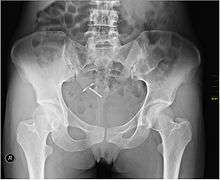

An intrauterine device (IUD or coil)[1] is a small contraceptive device, often 'T'-shaped, often containing either copper or levonorgestrel, which is inserted into the uterus. They are one form of long-acting reversible contraception which are the most effective types of reversible birth control.[2] Failure rates with the copper IUD is about 0.8% while the levonorgestrel IUD has a failure rate of 0.2% in the first year of use.[3] Among types of birth control they, along with birth control implants, result in the greatest satisfaction among users.[4] In 2007, IUDs were the most widely used form of reversible contraception, with more than 180 million users worldwide.[5]

Most copper IUDs have a plastic T-shaped frame that is wound around with pure electrolytic copper wire and/or has copper collars (sleeves). The arms of the frame hold the IUD in place near the top of the uterus. The Paragard TCu 380a measures 32 mm (1.26") horizontally (top of the T), and 36 mm (1.42") vertically (leg of the T).

The invention of the copper IUD in the 1960s brought with it the capital 'T' shaped design used by most modern IUDs. U.S. physician Howard Tatum determined that the 'T' shape would work better with the shape of the uterus, which forms a 'T' when contracted. He predicted this would reduce rates of IUD expulsion.[47] Together, Tatum and Chilean physician Jaime Zipper discovered that copper could be an effective spermicide and developed the first copper IUD, TCu200. Improvements by Tatum led to the creation of the TCu380A (ParaGard), which is currently the preferred copper IUD.[47]